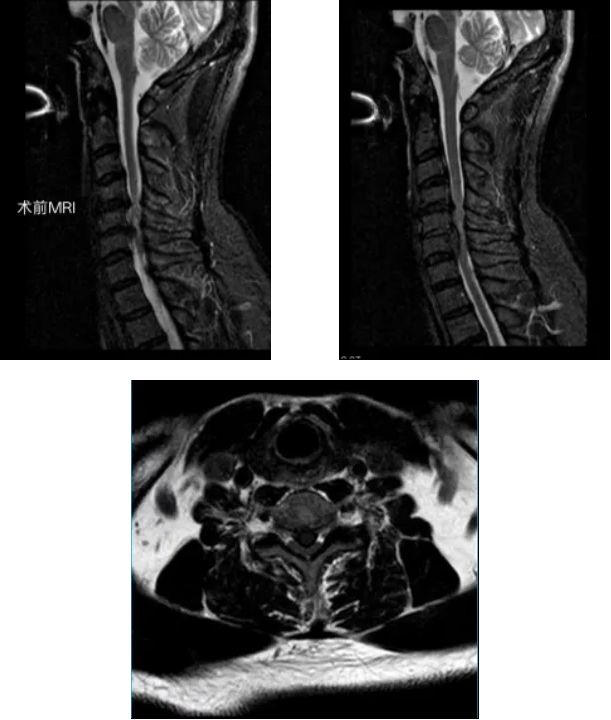

经详细问诊与影像检查,李永革主任很快锁定了“元凶”:颈椎MRI显示,徐先生的颈4/5、颈5/6、颈6/7椎间盘突出,其中颈5椎间盘已脱出,严重压迫脊髓,确诊为脊髓型颈椎病。

这是一种颈椎病中最需警惕的类型,因颈椎退变导致椎间盘突出或骨赘增生,直接压迫脊髓或影响其血供,引发神经功能障碍。典型症状包括:

面对徐先生明确的脊髓压迫和神经损伤,必须尽快手术减压。李永革主任团队经周密评估,为患者量身定制了方案:采用 UBE(单侧双通道内镜)技术施行颈前路微创减压融合术。